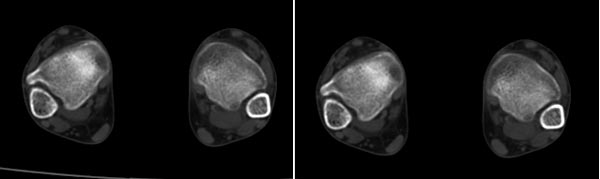

x线检查月前片示双踝关节骨质未见明显异常。一月后肿胀大部消失,疼痛稍有好转,摄片示两侧骨下段条带状高密度影,边界尚清。ct扫描示两侧胫骨下段骨皮质增厚不明显,髓腔内密度显示磨玻璃样增高,髓腔显示狭窄。

双侧胫骨远端松质骨内见不规则密度增高影,且均以内侧为主,内侧骨皮质边缘欠清晰.临床提示月前稍运动后踝关节肿大。我考虑双侧胫骨低毒感染。

x线检查一个月前示双踝关节骨质未见异常。一个月后肿胀大部消失,疼痛稍有好转,摄片示两侧胫骨下段横行条状高密度影,边界较清。ct扫描示:两侧胫骨下段未见骨皮质增厚,两胫骨下段近骨端处可见骨小梁增粗但纹理尚清晰,未见明显骨质破坏,邻近关节及关节囊未见明显异常,软组织内未见异常.综上所诉考虑1.低毒感染所致,2.假性痛风

x线片表现为双侧胫骨下端粗条状磨玻璃样增高密度影,并可见骨皮质稍不连续。ct表现为双侧胫骨下端髓腔内磨玻璃样增高密度影,未见明显骨皮质不连续(可能与扫描体位有关)。

本例应该考虑为双侧胫骨下端应力性骨折。

现在看来,该患者确实是疲劳性骨折,这几个月来已经差不多好了,线状影也基本消失了,下次发图片给各位战友看。但是很纳闷他工作轻松,又没有什么剧烈运动。